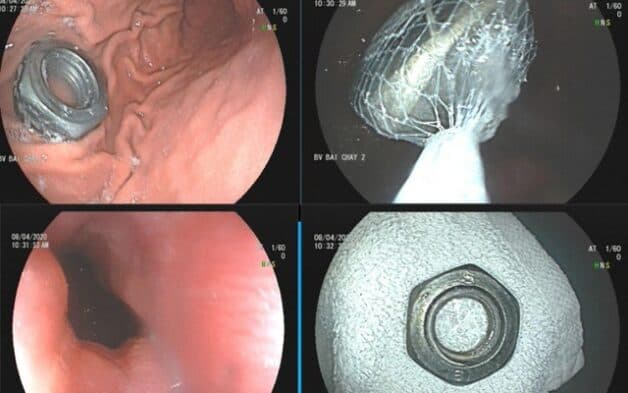

Hình ảnh dị vật trong họng (Nguồn: VTV Sức khỏe)